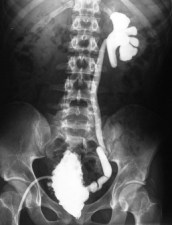

la rétention urinaire et les infections sont responsables d’une insuffisance rénale et d’une hypertension artérielle chez de trop nombreux patients porteurs de myéloméningocèle. l’insuffisance rénale terminale peut nécessiter la dialyse voire la transplantation rénale à condition que les problèmes de reflux et d’infection soient corrigés.

pour une femme porteuse de myéloméningocèle, la grossesse risque d’être compliquée d’infection urinaire de poussée tensionnelle. l’accouchement naturel pose le problème de déformation du bassin et d’une insuffisance de poussée abdominale. Par ailleurs l’anesthésie péridurale n’est pas possible.